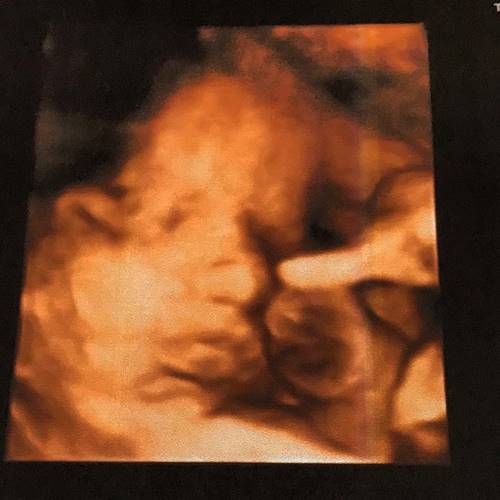

No Instagram, a jornalista também compartilhou com seus seguidores, nesta terça (11), um registro da ultrassom 4D do herdeiro: “CUIDADO!! Fofura excessiva passando pela sua timeline!”